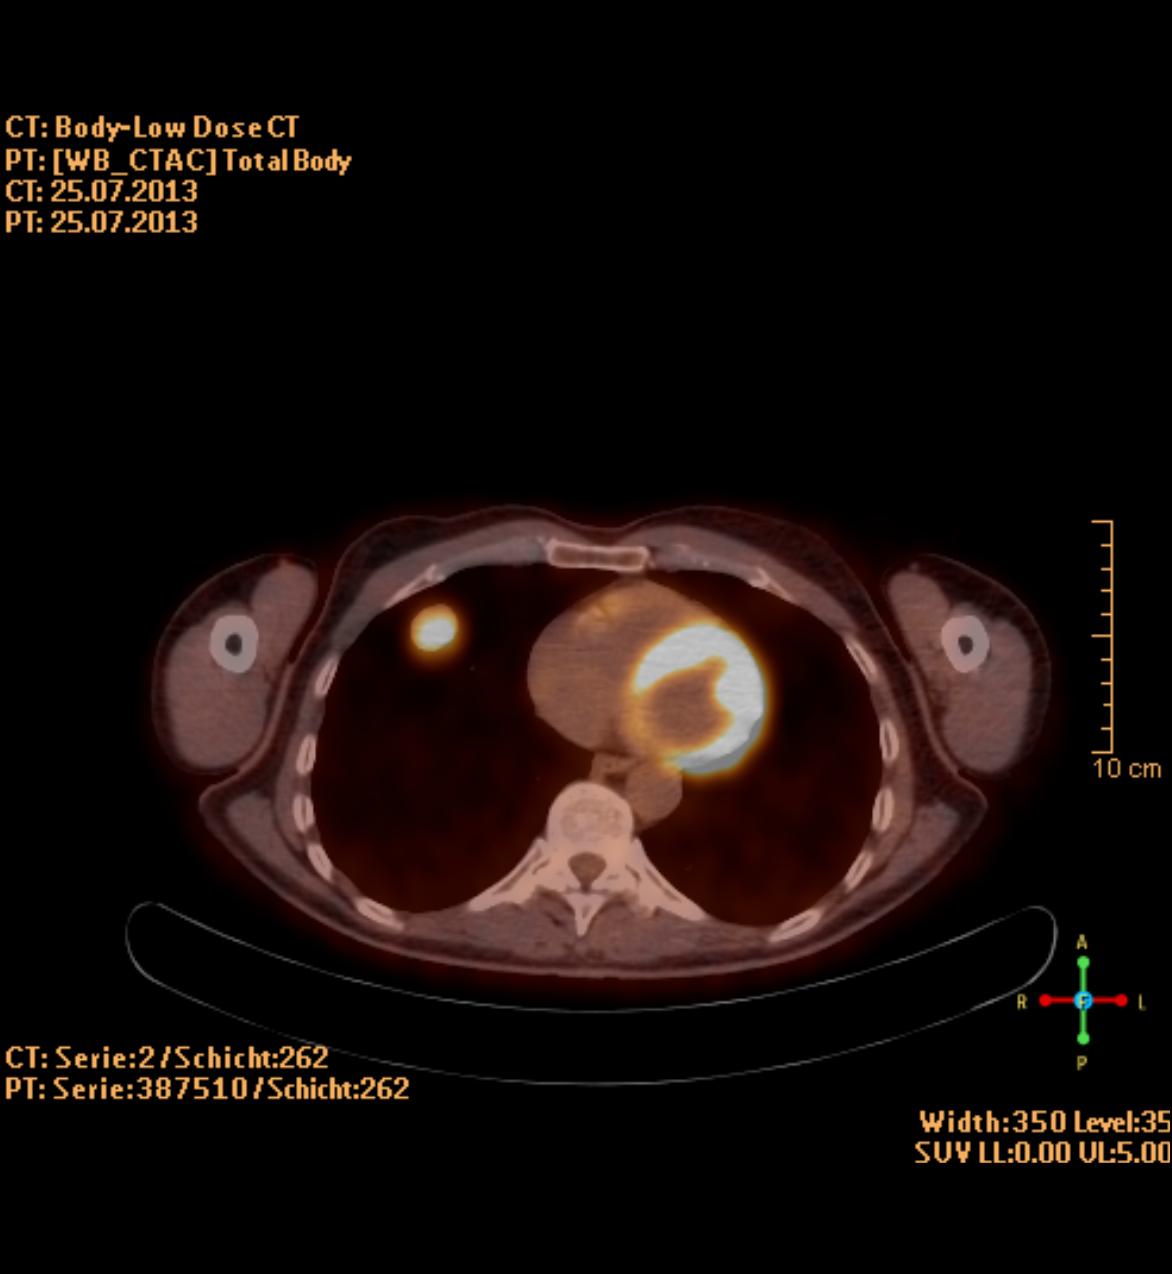

Die PET/CT ist in der Medizin derzeit die modernste zur Verfügung stehende bildgebende Untersuchung in der Diagnostik von Tumorleiden. Sie ermöglicht oft, sehr kleine Herde früher als mit anderen Verfahren wie Kernspintomographie (MRT) oder alleiniger Computertomographie (CT) zu entdecken. Ein besonderer Vorteil des Verfahrens besteht in der Kombination zweier bildgebender Verfahren, die sich perfekt ergänzen. Durch die CT Technik können Körperregionen und mittlerweile auch der gesamte Körper als vollständiger, lückenloser Datensatz erfasst werden. Dadurch entstehen Bilder in bis dahin ungeahnter Schnelligkeit und Qualität. Im PET werden im Gegensatz zum CT in erster Linie funktionelle Stoffwechselvorgänge im Körper dargestellt. Dazu wird Ihnen radioaktiv markierter Zucker (Glucose) in minimaler Menge in eine Vene injiziert. Die Verteilung im Körper wird mit einer speziellen Kamera (PET/CT-Scanner) gemessen, die Schnittbilder des Körpers gewinnt.

Die Glucose wird mit dem Radionuklid Fluor-18 markiert, das eine Halbwertzeit von 110 min hat. Das bedeutet, dass alle 2 Stunden die Radioaktivität um die Hälfte abnimmt. Zusätzlich wird innerhalb der ersten 2 Stunden ein Großteil der Radioaktivität über den Urin ausgeschieden. Insgesamt ergibt sich daraus eine durchschnittliche Strahlenbelastung von 6 mSv. Durch die PET wird also das Doppelte der natürlichen jährlichen Strahlenbelastung verursacht.

Zusammen mit der PET wird in der gleichen Untersuchung eine Computertomographie (CT) durchgeführt. Je nach Fragestellung und wenn schon Voraufnahmen vorhanden sind, wird das CT meist als Niedrig-Dosis CT ohne Röntgenkontrastmittel gefahren, d.h. mit niedriger Strahlenbelastung aber eingeschränkter Erkennbarkeit von anatomischen Details.

Ein Hybridgerät zwischen PET und CT in 64-Zeilen Technik wie am Klinikum Ludwigshafen kombiniert also in idealer Weise die detailgerechte hoch ortsaufgelöste Abbildung morphologischer und funktioneller Krankheitsaspekte insbesondere im Bereich der Onkologie.

- Nach einem Informations- und Aufklärungsgespräch spritzt der Arzt Ihnen die radioaktiv markierten Zucker in die Vene. Die Glucose muss sich in einer Ruhezeit von 50 min im Körper verteilen. Erst danach erfolgt zuerst die CT, direkt anschließend die Aufnahmen mit der PET-Kamera. Die beiden Untersuchungen zusammen dauern ca. 20 Minuten. Während der Untersuchung sollten Sie ruhig atmen und sich möglichst wenig bewegen.